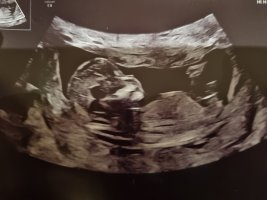

hvor mange uker og dager? umulig å si ut i fra 3D bildene, men synes jo at dette ser ut som klitoris og kjønnslepper.

Ser ut til at det blir en jente etter OULJeg vil endre svare mitt, at det er en jente, jeg tror det er den hula rett bak nuben som er blæra ikke den litt nedenfor som jeg først tenkte.

Ingen indikasjon på gutt her.Jeg leste feil på posten din (hvis du allerede har lest svaret) gratulerer med jenteSer ut til at det blir en jente etter OL!Ingen indikasjon på gutt